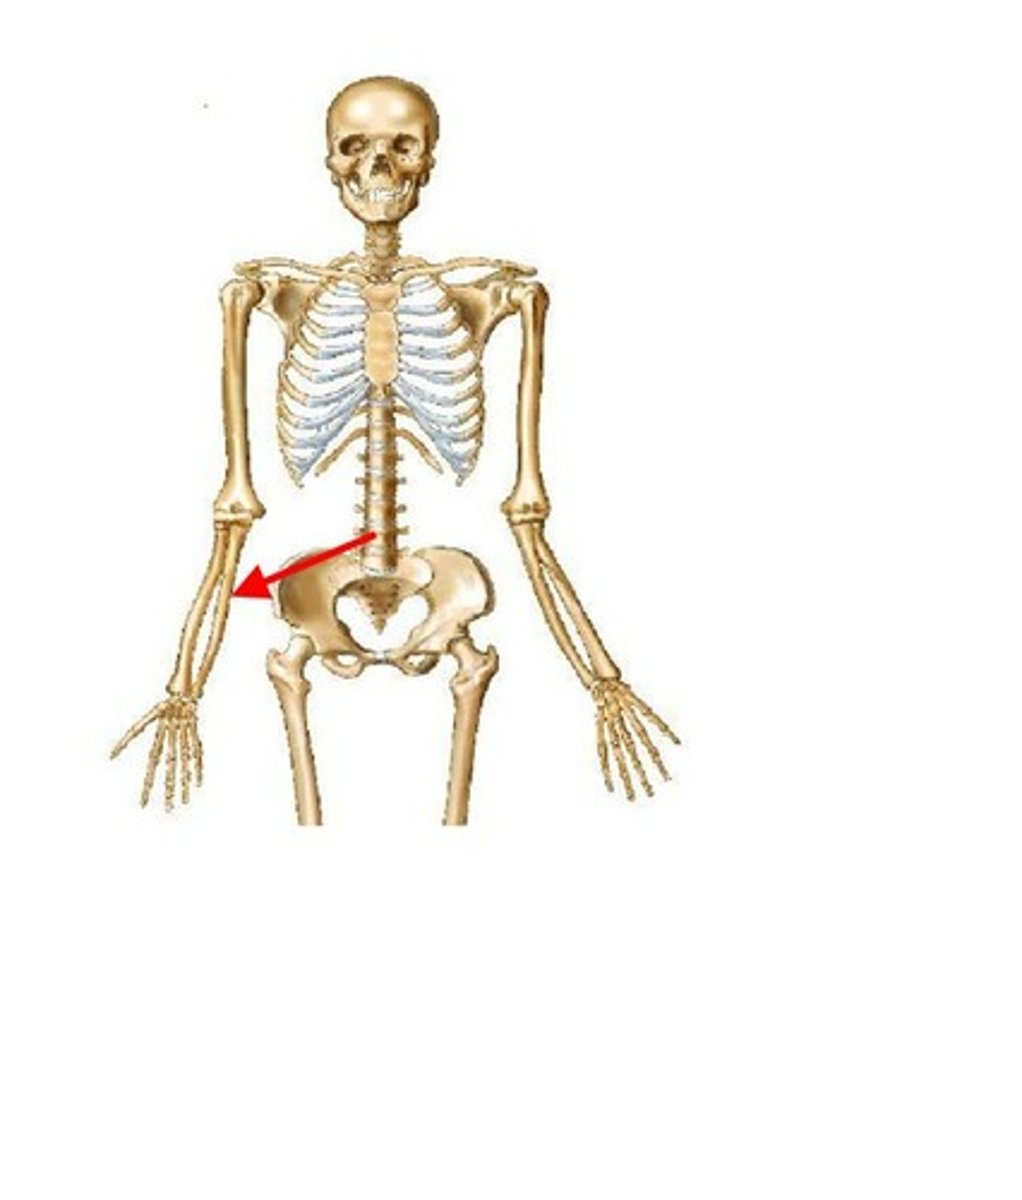

clavicle

ID red bone

carpals

ID red bones

humerus

ID red bone

metacarpals

ID red bones

phalanges

ID red bones

radius

ID red bone

ulna

ID red bone